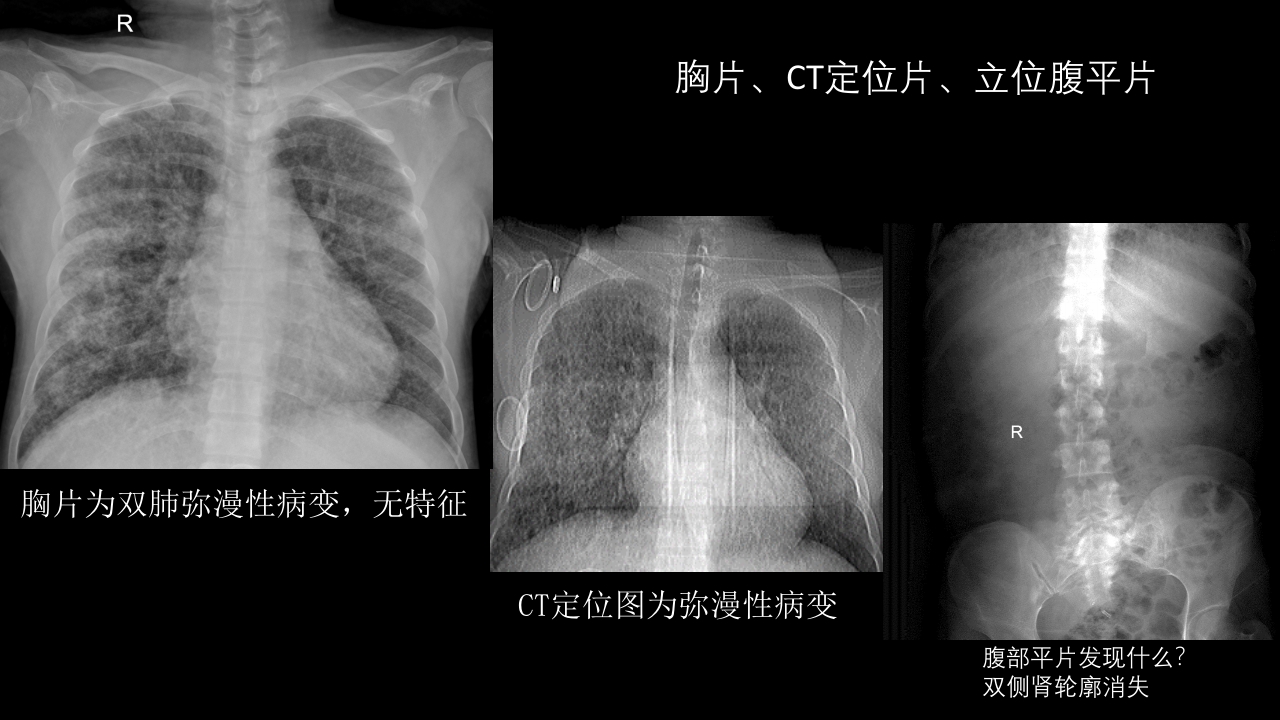

肺淋巴管肌瘤病合并双侧巨大肾血管平滑肌脂肪瘤(X线、CT、MR)